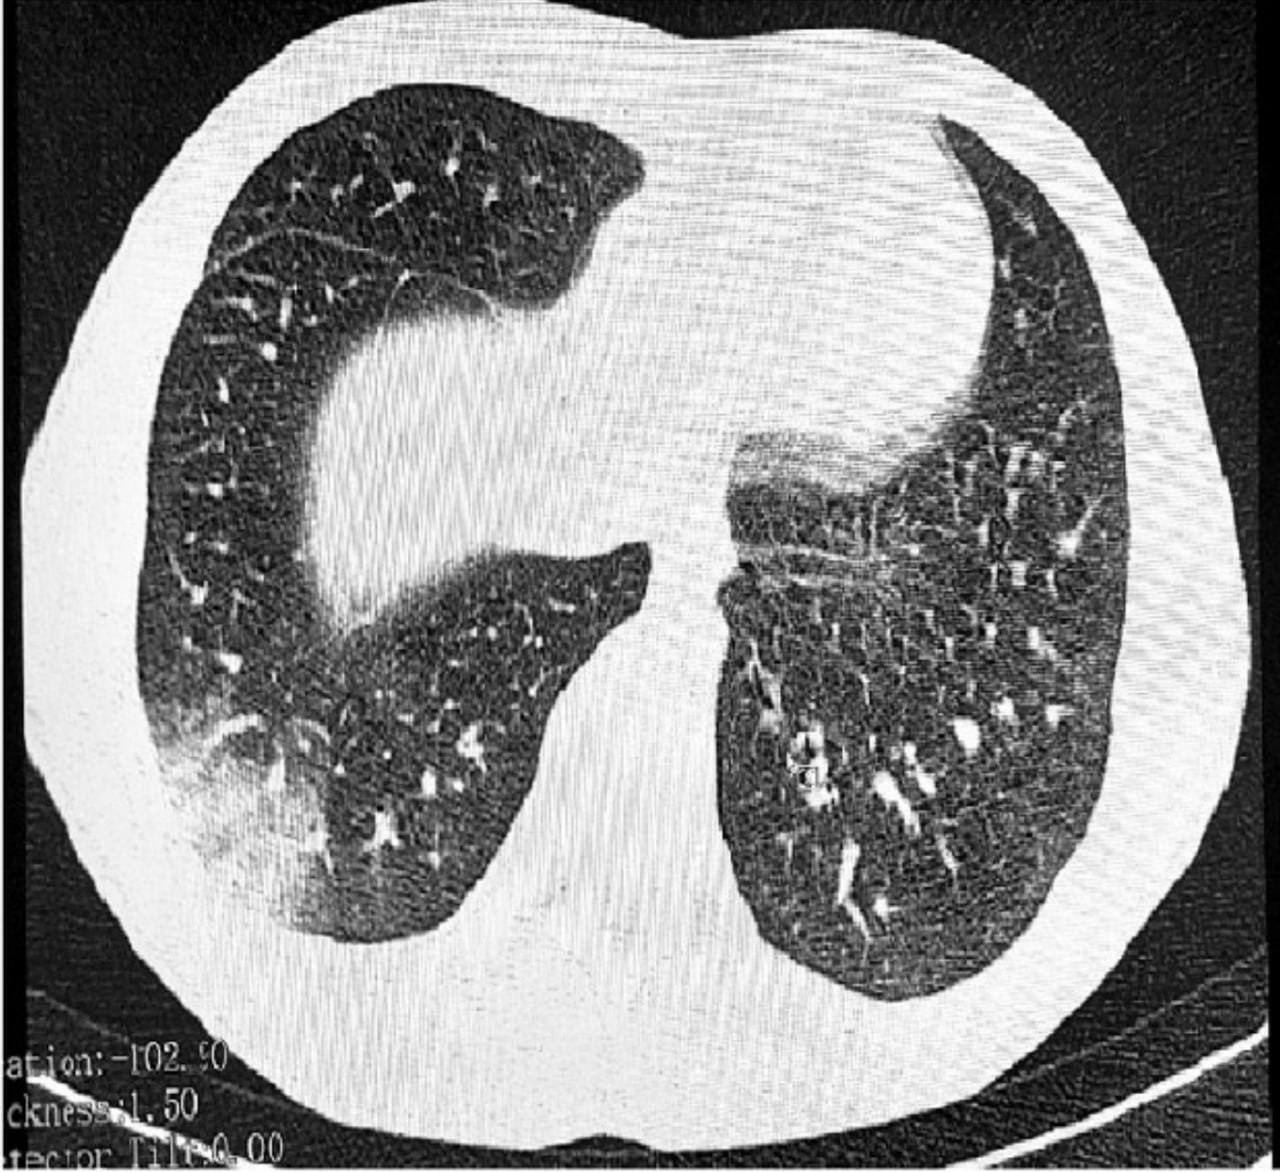

Речь идет о EVALI - так называют облитерирующий бронхиолит, поражающее мелкие бронхи. Болезнь может грозить каждому вейперу, ее даже называют неизлечимой формой рака, так как на данный момент не существует эффективного метода лечения этого заболевания.